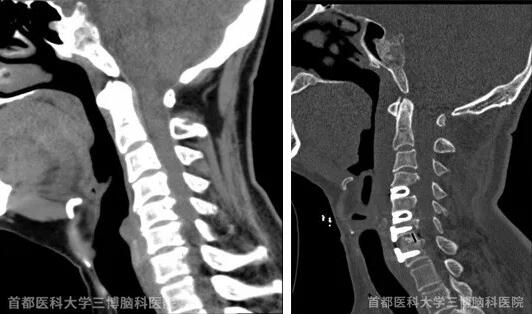

患者5年前左手手指出现麻木,当地医院诊断为颈椎病,给予口服药物治疗后无好转,3年前出现颈肩部不适,伴有间断左前臂疼痛,劳累后加重,今年4月到当地医院检查提示颈椎生理曲度反曲,颈椎骨质增生,颈3—4椎间盘突出,颈5—6、颈6—7间盘突出。颈5椎体骨质硬化。为手术治疗颈椎病找到三博范涛教授。

术前影像资料(左) 术后影像资料(右)

范涛教授采取颈前右侧入路的方式,为他做了颈椎间盘摘除+椎间固定融合术,血管神经保护完好,患者术后症状消失,康复后出院。范涛教授特别提醒,从颈部前方入路相对于后边入路有较大的难度和手术风险,颈椎病一定要及早治疗,该患者拖延了几年,造成颈椎没有生理曲度,几乎成了一条直线。如果早点治疗,手术难度和风险都会降低。